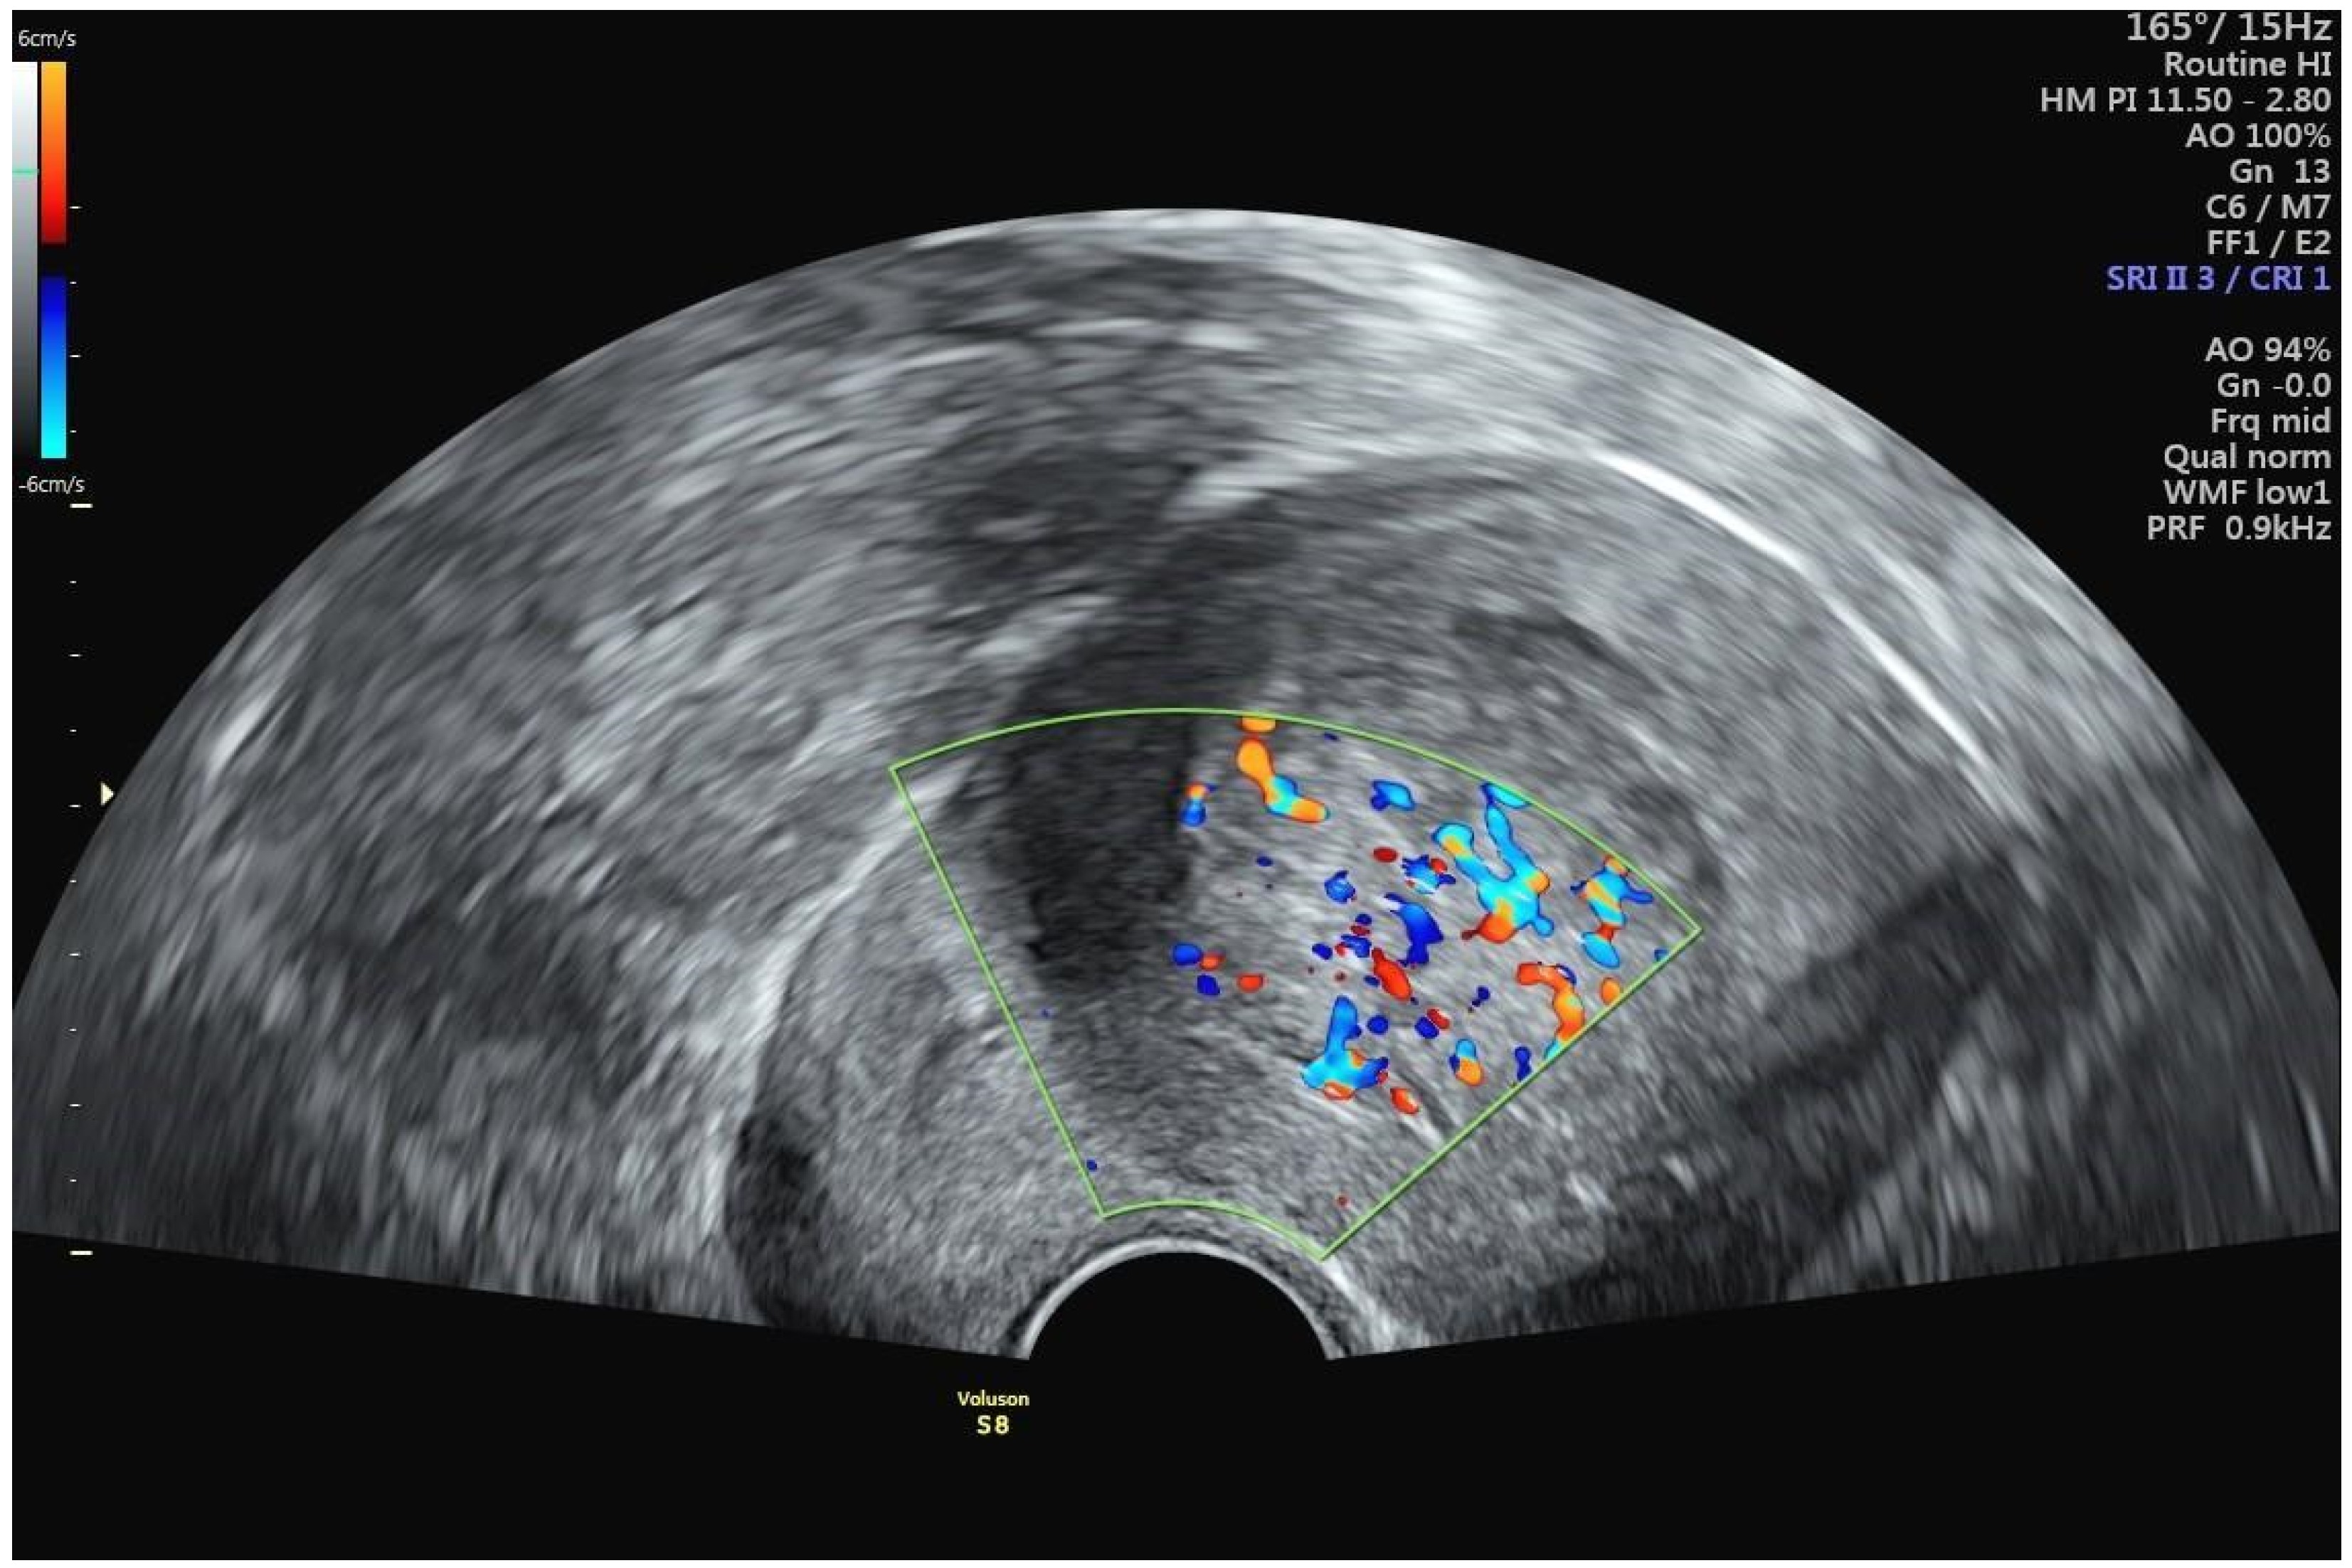

A 42-year-old woman presented at a clinic in Switzerland with a chief complaint of heavy menstrual bleeding for more than one year. She had an established diagnosis of uterine fibroids, most notably an International Federation of Gynecology and Obstetrics (FIGO) type 2 submucous fibroid that was first diagnosed 4 years earlier. At the time of that original fibroid diagnosis, the myoma had measured 2.7 cm, but in the interim had increased in size to 3.8 cm (Figure 2). Perfusion on color Doppler was increased and was centrally located (Figure 3). The patient had been suffering from heavy menstrual bleeding for over a year and wished to preserve her fertility. Thus, a combination of transvaginal fibroid resectoscopy and transcervical fibroid ablation (TFA) with the Sonata System was chosen.

In general, fibroid biopsy is not performed prior to transcervical fibroid ablation with the Sonata System but may certainly be performed at a physician’s discretion. In hindsight, the only feature consistent with uterine sarcoma was the increased internal vascularization on color Doppler ultrasound (Figure 3). Resistive index assessment was not performed. The value of diffusion-weighted MR imaging and other imaging techniques for distinguishing between uterine fibroids, STUMPs, and uterine sarcomata remains to be established, despite several promising studies [18,19,20].

Figure 3. Color Doppler sonography of FIGO type 2 uterine fibroid, demonstrating unusual central (rather than peripheral) perfusion.